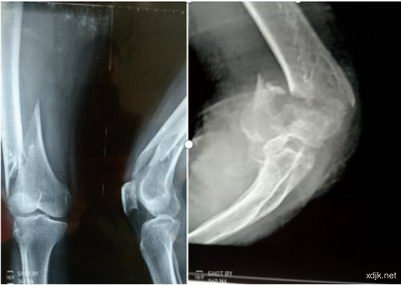

2、曹元吉,男,85岁,电话;0318*****78,衡水市冀州区小寨乡北小位村人,因滑倒摔伤,致左胫骨平台纵裂10余公分长,左髌骨成三瓣粉碎性骨折,如在医院里治疗必定是固定手术,一年也恢复不了正常活动。2015年2月3日来诊,未做任何固定,用特效接骨汤,接骨散内服,外贴生鲜膏仅两周就可以下床逐渐活动了,用药3天,髌骨长住,用药三周告愈。未留任何后遗症,曹老先生是一位退休老医生,逢人就说;我干了一辈子医生,没听说过有这等快速治骨折的药物。这是一例老年人骨折,具有一定的代表性,类似案例也接诊过很多。